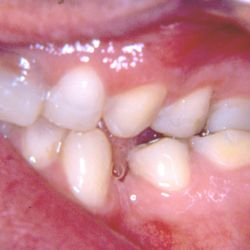

Ο κάτω γομφίος σε αυτή την νεαρή ασθενή έχει απονευρωθεί.

Για να εξασφαλίσουμε την καλή πρόγνωση του δοντιού και ταυτόχρονα την προστασία του από πιθανό κάταγμα, αποφασίστηκε η τοποθέτηση ενός επενθέτου εργαστηριακής σύνθετης ρητίνης.

Η διαδικασία ολοκληρώθηκε σε 2 ραντεβού, ενώ ο τροχισμός του δοντιού διατηρήθηκε στο ελάχιστο δυνατό.

Η εναλλακτική λύση θα ήταν να τροχιστεί εντελώς το δόντι και να τοποθετηθεί μια στεφάνη, οδηγώντας όμως έτσι σε αφαίρεση μεγάλης ποσότητας οδοντικής ουσίας.